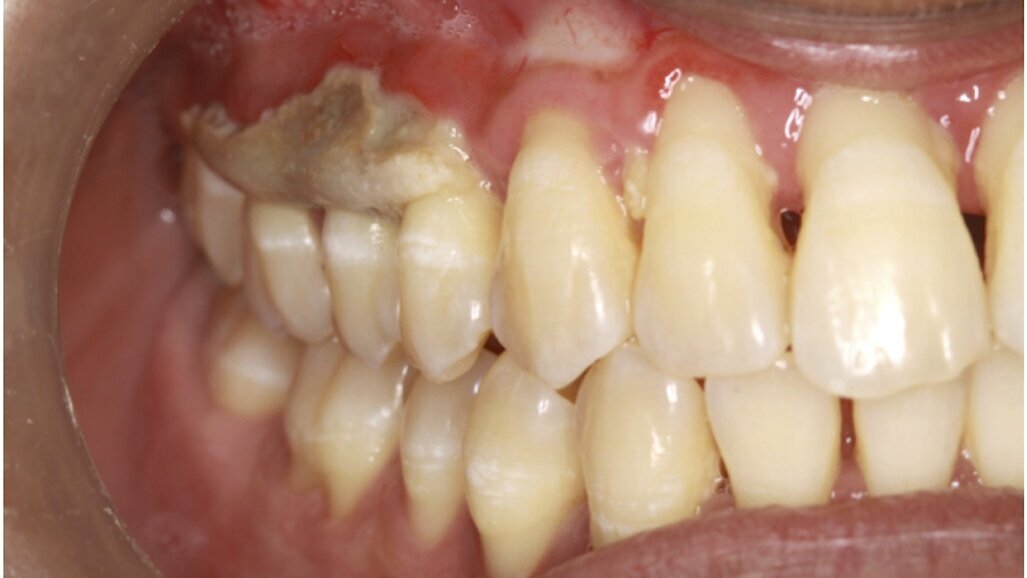

Al examen clínico intraoral se observa por vestibular tejido óseo expuesto a nivel de premolares y molares superiores derecho (Figura 1). Del lado izquierdo, entre primer premolar a segundo premolar se observa hueso vestibula,r conservándose las papilas, y el tejido blando circundante al hueso expuesto se observa inflamado y presenta sangrado espontaneo (Figura 2).

Se realizó anestesia troncular e infiltrativa con odontocaína al 3% (New Stetic, Colombia), se retiraron los fragmentos de tejido necrótico y enviados a patología para biopsia. La paciente fue manejada con Amoxtrix 500 mg (Laboratorio Farpag, Colombia), cada 8 horas por 7 días, k-trix (Laboratorio Farpag) lavado 2 veces al día, k-cit (Laboratorio Farpag) aplicado en la herida 3 veces al día.

A los 12 días se realizó un control, observándose mejoría y recuperación del tejido blando por vestibular (figuras 3 y 4).

El diagnóstico emitido en la biopsia fue osteonecrosis maxilar superior derecho e izquierdo.